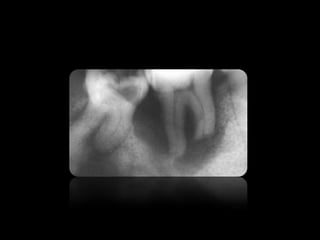

CARIES